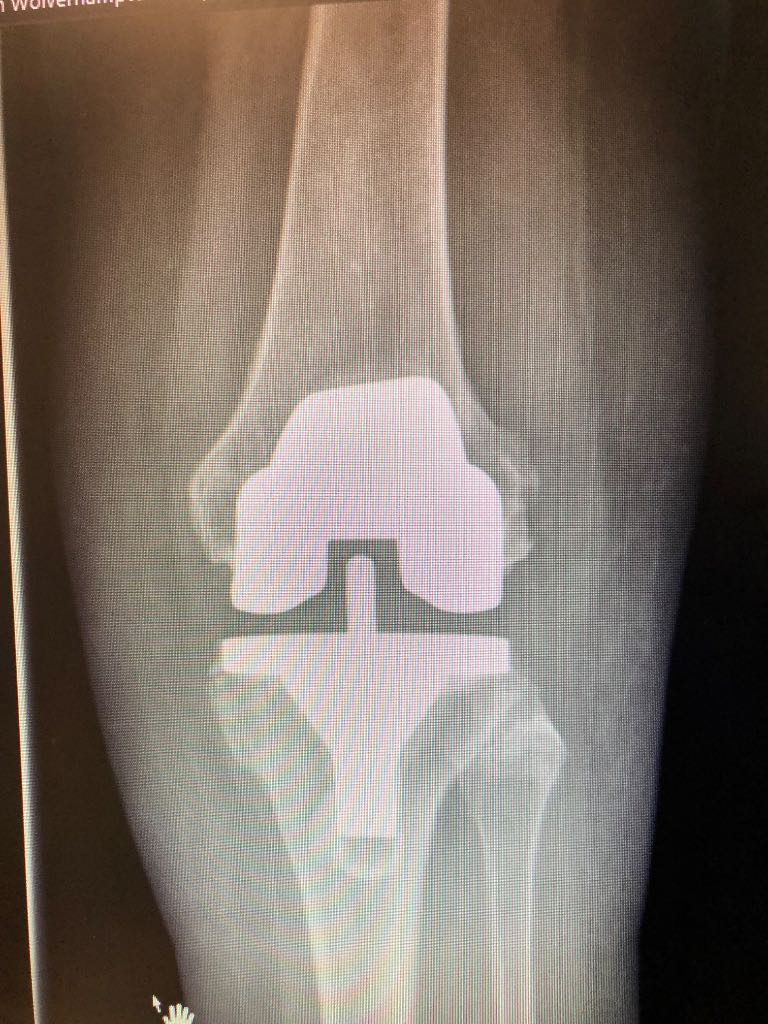

He performs a large number of partial knee replacements, many of which can be carried out as day case procedures. These minimally invasive operations typically allow faster recovery and now offer durability comparable to total knee replacement in suitable patients.

Knee surgery; Hip replacement surgery; Sports knee injuries; spinal pain; Sciatica; dislocating knee; knee deformity ; multi ligament surgery ; patella instability ; complex deformity surgery ; partial knee replacements ; unicompartmental knee replacement.